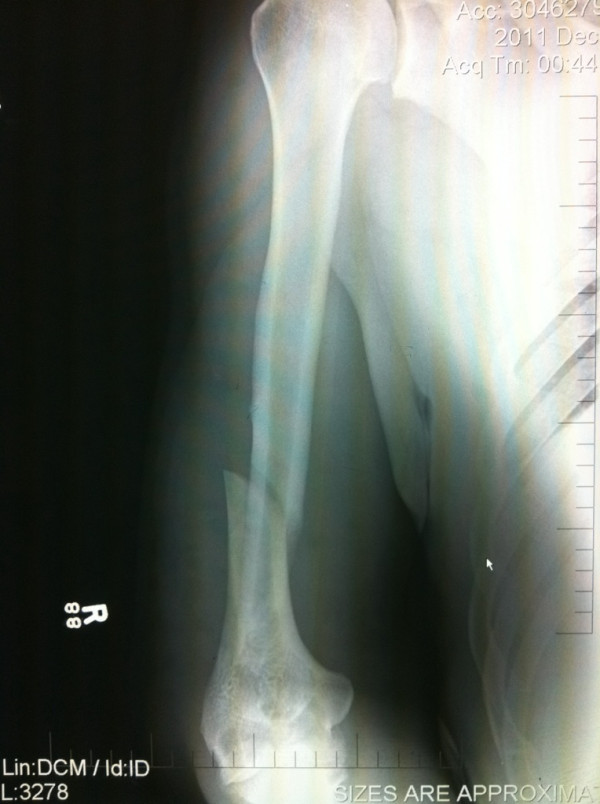

Ο Nogueira δεν ήθελε να παραιτηθεί αναγκάζοντας το διαιτητή να διακόψει τον αγώνα βλέποντας πως ο αγκώνας του ήταν σε… ασυνήθιστη θέση. Τόσο η εικόνα της ακτινογραφίας, όσο και οι 16 βίδες που τοποθετήθηκαν στο χέρι του Βραζιλιάνου, μαρτυρούν το μέγεθος του φρικιαστικού τραυματισμού.